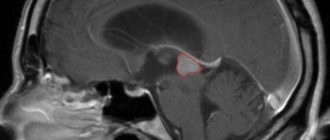

Признаки кисты гипофиза и методы избавления от нее Кистой гипофиза называется полость, заполненная спинномозговой